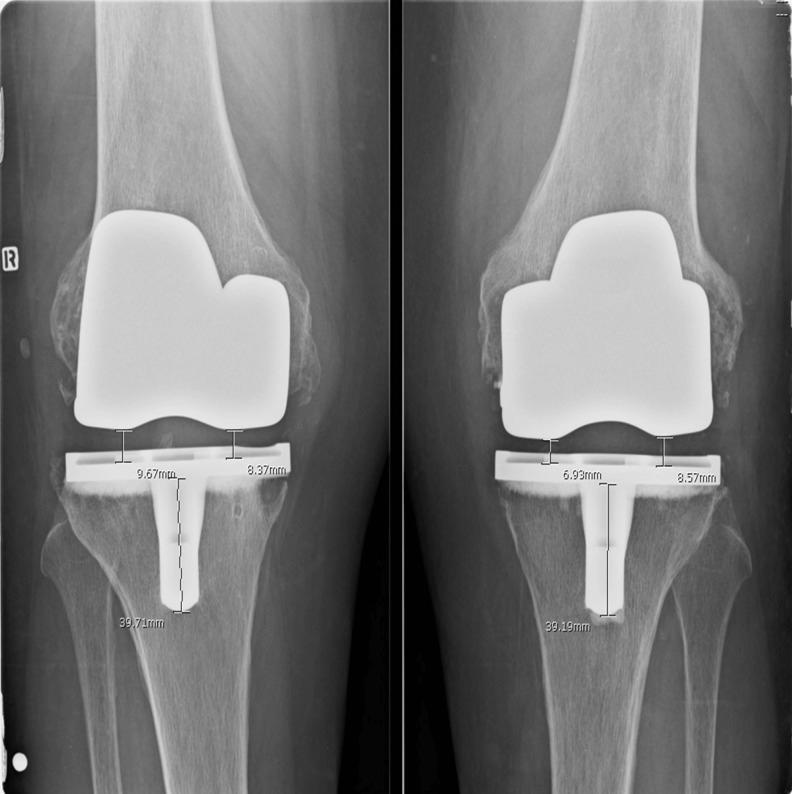

15-17 岁行全膝关节置换术:假体设计是否影响疗效?

Total knee arthroplasty at 15-17 years: does implant design affect outcome?

A study was conducted to compare minimum 15-year survivorship and outcome of the Genesis I and II implants for total knee arthroplasty (TKA).

We retrospectively reviewed 245 consecutive TKA implanted between January 1995 and October 1997. Genesis I was implanted in 156 knees and Genesis II in 89 knees.

At 15-17 years, 75 patients (31%) had died, 28 patients (11%) were lost to follow-up and 11 TKA were revised (4.6%), including ten Genesis I (6.4%) and one Genesis II (1.1%); 131 TKA (53%) were available for follow-up. Cumulative survivorship was 92.4% at 15.7 years. Survival in patients <69 years at surgery was lower (88.0%) compared with patients ≥69 years (98.5%; p = 0.023). In patients <69 years, Genesis I survival (84.3%) was worse compared with Genesis II (97.1%) (p = 0.018). Polyethylene (PE) Insert thickness ≤11 mm had significantly better survivorship (97.1%) compared with PE >11 mm (56.7%) (p < 0.0001) CONCLUSIONS: At a minimum of 15 years, the overall (92.4%) survivorship of Genesis TKA was good, with excellent (98.1%) survivorship of the Genesis II design. Revision rates were higher with Genesis I in the younger age group and with insert thickness >11 mm, possibly due to longer shelf life of less frequently used sizes.